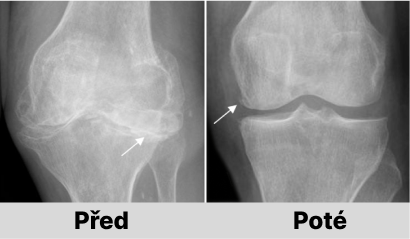

Jaroslava Melicharová: Určitě to možné je. Pokud nedošlo k nevratným patologickým změnám v kostech, lze vše napravit odstraněním příčiny pomocí AntiZynt. Náš výzkum dokazuje, že již za 1-1,5 měsíce nepřetržitého užívání AntiZynt je možné obnovit klouby i u těžkých forem osteoartrózy a artrózy.